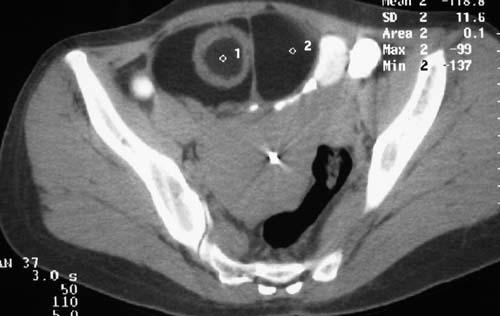

一、女,43岁,下腹部不适,子宫增大并可触及一硬物,活动度大。

二、男,55岁,排尿困难两年,b超示盆腔不均质包块,ct值约27hu.

例2:盆腔占位,肿块密度欠均匀,其内有钙化影,其边界清晰,膀胱前上壁受压,膀胱壁尚清晰,考虑为不典型畸胎瘤压迫膀胱可能,建议增强扫描吧。

病例1,盆腔畸胎瘤并子宫肌瘤;病例2,囊性肿块,周围有壳状钙化,膀胱受压改变,考虑:脐尿管囊肿并感染,畸胎瘤?